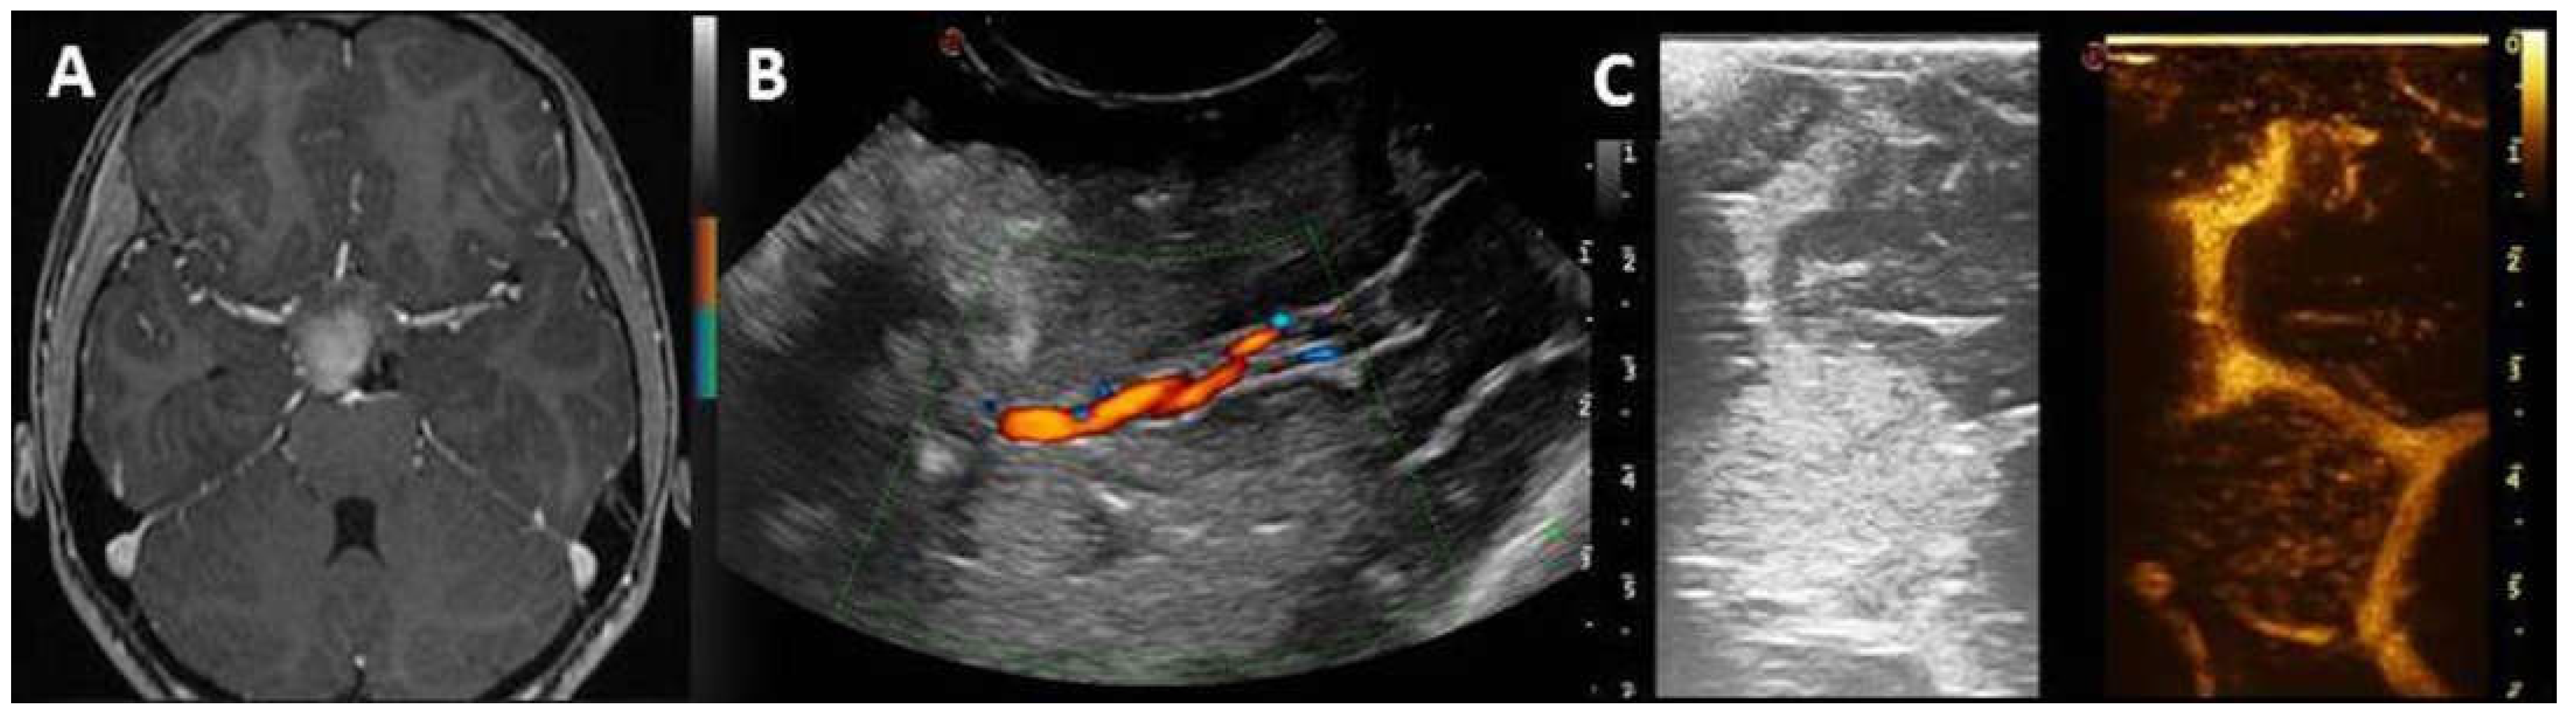

| Definition | Vascular relationship |

|

| Definition | Vascular pattern |